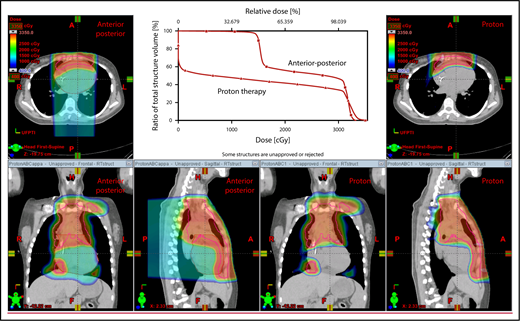

The plan target is the CTV; when the treatment area is affected by breathing motion, the plan target is the internal target volume (ITV), which encompasses the motion of the CTV depicted on 4D CT scans. Alternately, if treatment is to be given with DIBH, an ITV can be derived from the positions of the CTV reproduced from multiple DIBH scans. For lateral beam shaping, margin expansion to form the PTV accounts for setup uncertainty, and interfractional variability in anatomy is applied to the CTV/ITV. Patient-specific beam collimators conform the dose laterally to the PTV, with a margin for penumbra. Depending on the target depth and adjacent tissue, these margins vary from 5 to 10 mm. Range compensators are designed for each beam to conform the dose distally to the CTV/ITV. Range compensator smearing within a radius appropriate for setup tolerances and tissue motion is applied to account for proton range changes caused by density changes in the beam path. In addition, along each beam, distal and proximal margins are set to the CTV/ITV to compensate for proton range uncertainties, as described under “Range uncertainties due to density variations.” Multiple beams (compared with 1 beam) can be used to increase dose conformality and reduce dose uncertainties by spreading the beams in various directions. The preference is to use anterior or posterior fields, rather than both, because of the need to avoid unnecessary beam through the heart (Figure 4).

An example of an approach using 2 anterior fields with proton therapy, which can better spare the heart and esophagus (right) compared with an anterior/posterior approach (left).